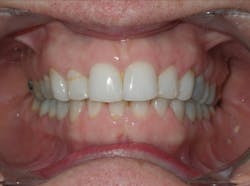

Case 2: 48-year-old female: 15-month clear aligner treatment. This case demonstrates an improvement in a remodeled alveolar complex and an increase in vertical dimension. Case and photos courtesy of Dr. Ben Miraglia.

Before: V-shaped arch. After: U-shaped arch.

Before: Severe deep bite. After: Improved vertical dimension.

Before: V-shaped arch. After: U-shaped arch; implant placed No. 14.